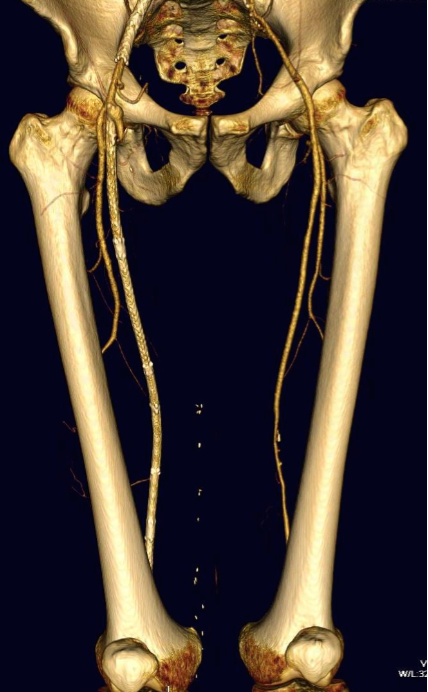

The patient is 70 year old woman with prior history of smoking who developed severe claudication and near rest pain. She was unable to walk more than 50 feet before having to stop due to severe leg pain. On exam, neither femoral artery pulses were palpable. PVR’s (pulse volume recordings) and ABI’s (ankle brachial index) are shown below.

PVR’s demonstrate the presence of severe inflow (aortoiliac occlusive disease or AIOD). CTA was acquired and the findings were consistent with the PVR’s.

There was diffuse bilateral iliac atherosclerotic plaque with occlusion of the right common femoral artery and left common and external iliac artery. The 3DVR (three dimensional virtual reality) reconstruction image below shows this as well as the abdominal and pelvic wall collaterals feeding the legs around the occluded iliofemoral system.

Plans were made to perform a hybrid common femoral and profunda femoral endarterectomy, remote external iliac artery endarterectomy (EndoRE), and common iliac artery stenting. The specific challenges to this case was getting into and staying in the true lumen. Typically, this is easiest to achieve from a left arm access with wires being pushed antegrade, but in a smaller person, particularly woman, this increases the chances for access site complications. My plan was to expose both common femoral arteries and get control of the external iliac arteries at the inguinal ligament and the profunda femoral arteries at the point the proximal plaque dissipated -typically at the second branch point, and then get micropuncture access of the right iliac system by accessing from the common femoral plaque. This would give me true lumen access, and with a sheath and curved catheter (VCF in this case, but a similarly shaped OMNI Flush catheter would do as well), wire access up and across the occluded left iliac system could be achieved and the wire retrieved from the left common femoral artery. This up and over access with the wire allows for control of the aortic bifurcation and both iliac systems.

The patient recovered well. I always use cell salvage -sometimes, profundaplasties can be bloody, particularly if they are in reoperative fields. The ABI’s and PVR’s at the ankles improved significantly.

The postoperative CTA shows good results as well. Below is the composite right and left centerline from aorta to the PFA’s.

The 3DVR reconstruction images are shown below, with the comparison to preop shown in the first image of this blog entry:

The pre and postoperative images of the centerlines (composited) are shown below: